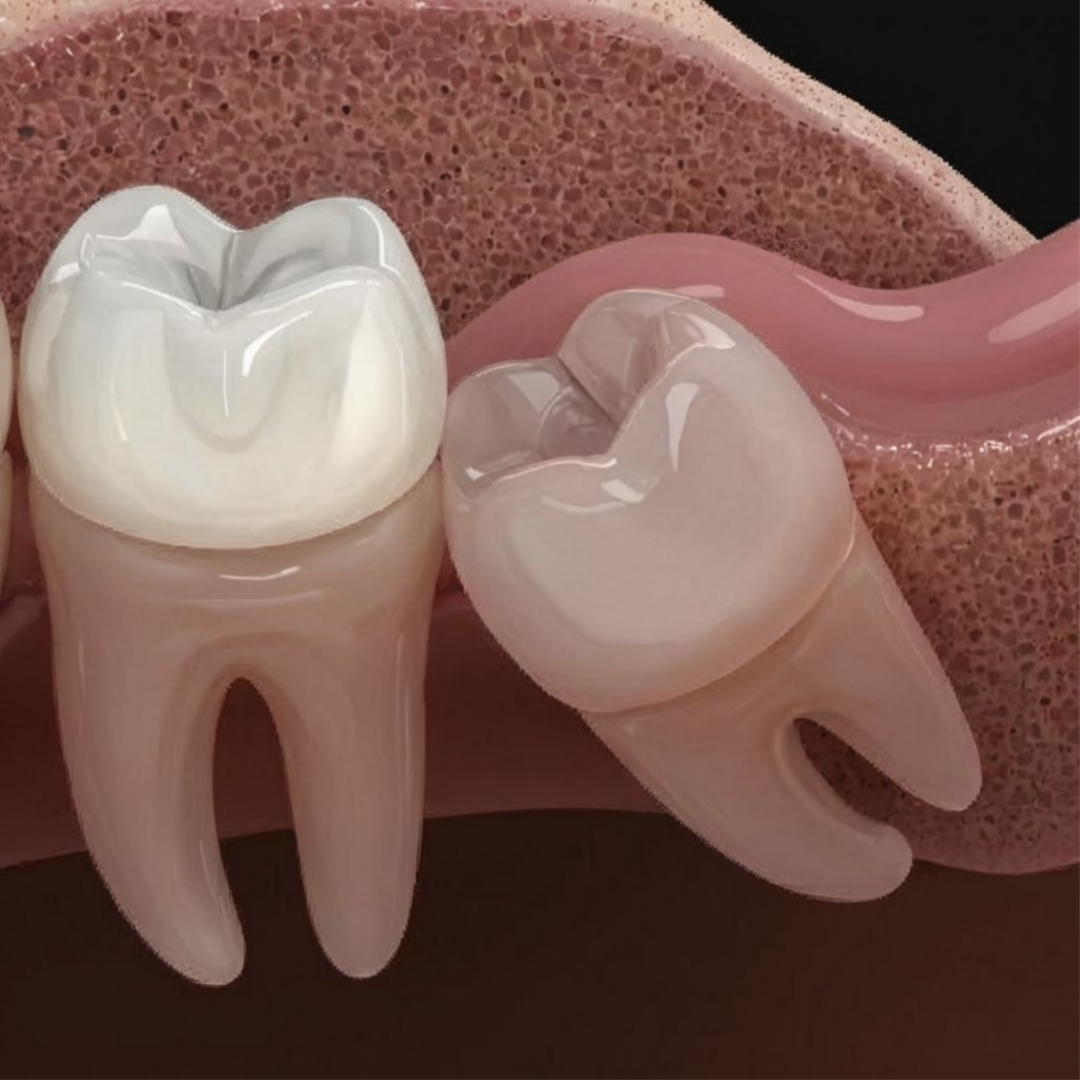

사랑니가 비스듬하게 누워있는 경우, 구강악안면외과 전문분야인 외과적 수술을 통해 사랑니를 발치합니다.

매복 위치에 따른 전문적인 추가 수술

사랑니는 매복위치에 따라 수술 난이도가 달라집니다. 보통은 잇몸수술을 동반하게 되고, 치아 분할이나, 뼈 삭제 과정 등이 필요하게 될 수 있습니다.

매복사랑니는 매복된 위치에 따라 난이도가 다릅니다. 보통 잇몸 수술을 동반해서 치아 분할, 골 삭제가 이뤄지므로 많이 불편할 수 있는 과정입니다. 최소절개, 최소삭제를 원칙으로 발치를 진행하여 수술 기간과 후유증을 최소화합니다.

사랑니 주변 치아를 밀어내어 주변 어금니까지 기울어지게 됩니다.

주변 치아를 밀어내어 치열이 삐뚤어지는 부정교합을 유발합니다.